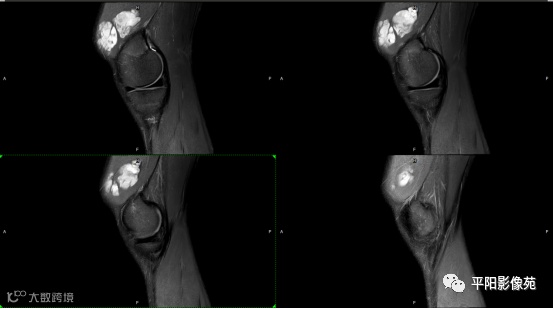

影像表现:

左膝关节股内侧肌内见多房样短T1长T2信号,内可见分隔,增强扫描明显强化,分隔未见明显强化,病灶局部与股骨远端分界不清。

MRI表现:好发于下肢, 较大病灶多为与肢体长轴一致的梭形, 边缘不清, 较小病灶呈类圆形, 边缘较清;②T1WI呈等或稍高信号, 病灶内部或边缘可见线条状或花边状高信号灶, 类似于皮下脂肪信号, T2WI上为明显高信号, 为本病特征性MRI表现;③病灶内静脉石及血管流空影为又一特征MRI表现;④GD-DTPA增强, 病灶明显强化, 其内低信号间隔无强化;⑤可见骨外形改变, 骨质增生及骨质吸收等表现。